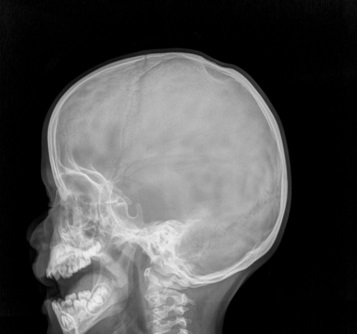

Se completó el estudio con una tomografía computarizada de cráneo (Fig. 2) con el objetivo realizar diagnóstico diferencial con otras patologías que pueden dar imágenes similares neoplasias, alteraciones postraumáticas, mielomeningoceles congénitos, osteomielitis, tumores de la bóveda craneal, metástasis. En la tomografía computarizada se observó una depresión que afectaba a la tabla externa del hueso parietal bilateral con extensión del defecto de 50 mm × 25 mm, confirmando el diagnóstico de foramen parietal magno. Dado las dimensiones del defecto se derivó a Neurocirugía para valorar cierre quirúrgico.

Figura 2. Reconstrucción de la tomografía computarizada en 3D donde se aprecia el defecto óseo a nivel de la calota de unos 5 cm